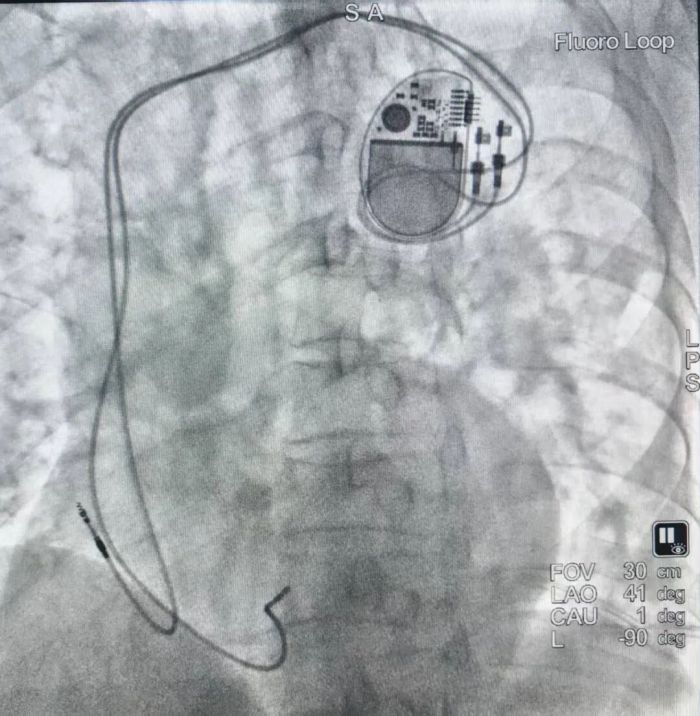

面对这一高难度病例,陈明鲜副主任带领团队沉着应对,对患者进行了全面评估,并据此制定了详尽且个性化的手术方案与应急预案。手术台上,团队凭借精湛的穿刺技术和清晰的影像引导,将心室与心房导线精准定位,起搏功能即刻反应良好。整台手术精准高效,术中出血量少,患者生命体征始终平稳。

起搏器顺利植入患者体内,起搏功能即刻反应良好